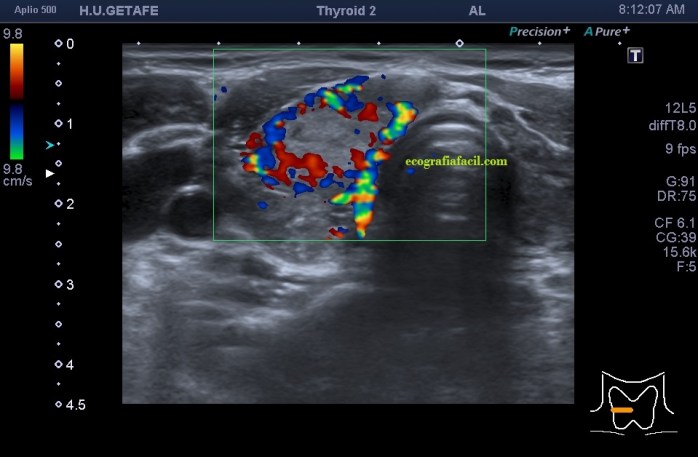

De la imagen 1 a 7 el protocolo habitual, el estudio particular del nódulo con medidas y aplicación del doppler demuestra el aspecto típico del Caballero Blanco.

De la 8 a la 11 estudio con Doppler.

- Doppler Color y Doppler Power aumentado de tamaño en el nódulo